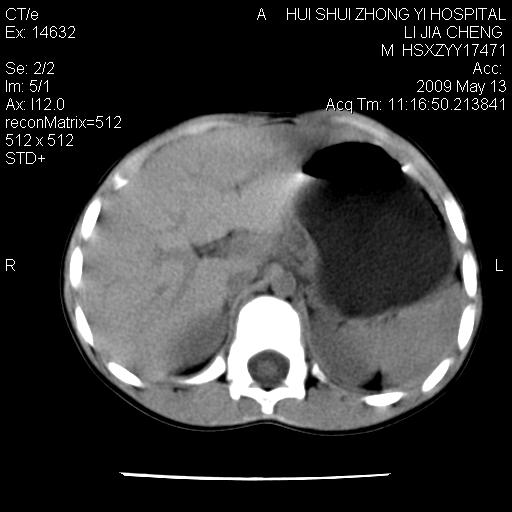

标题: PED1887:男性,6岁。反复脐周疼痛2年余。请各位老师看下腹 [打印本页]

标题: PED1887:男性,6岁。反复脐周疼痛2年余。请各位老师看下腹

该患者可自行好转,大小便未见异常,化验:便未见虫卵,血常规:wbc:8000;淋巴3600,中性45%

脂肪肉瘤可能性大,大血管边界不清,特别是腔静脉。不除外其他腹膜后肿瘤。

是不是有蛔虫哦,楼主图示块影前方肠管壁显著增厚,不除外慢性肠炎或肠壁占位,建议肠道准备后复查

肠道准备不足,im15---------------------18左侧腹腔病变?

肠管管壁均匀增厚,炎性可能

是小肠,壁稍厚可能是肠腔未很好充盈所致,腹部ct扫描未见明显异常。